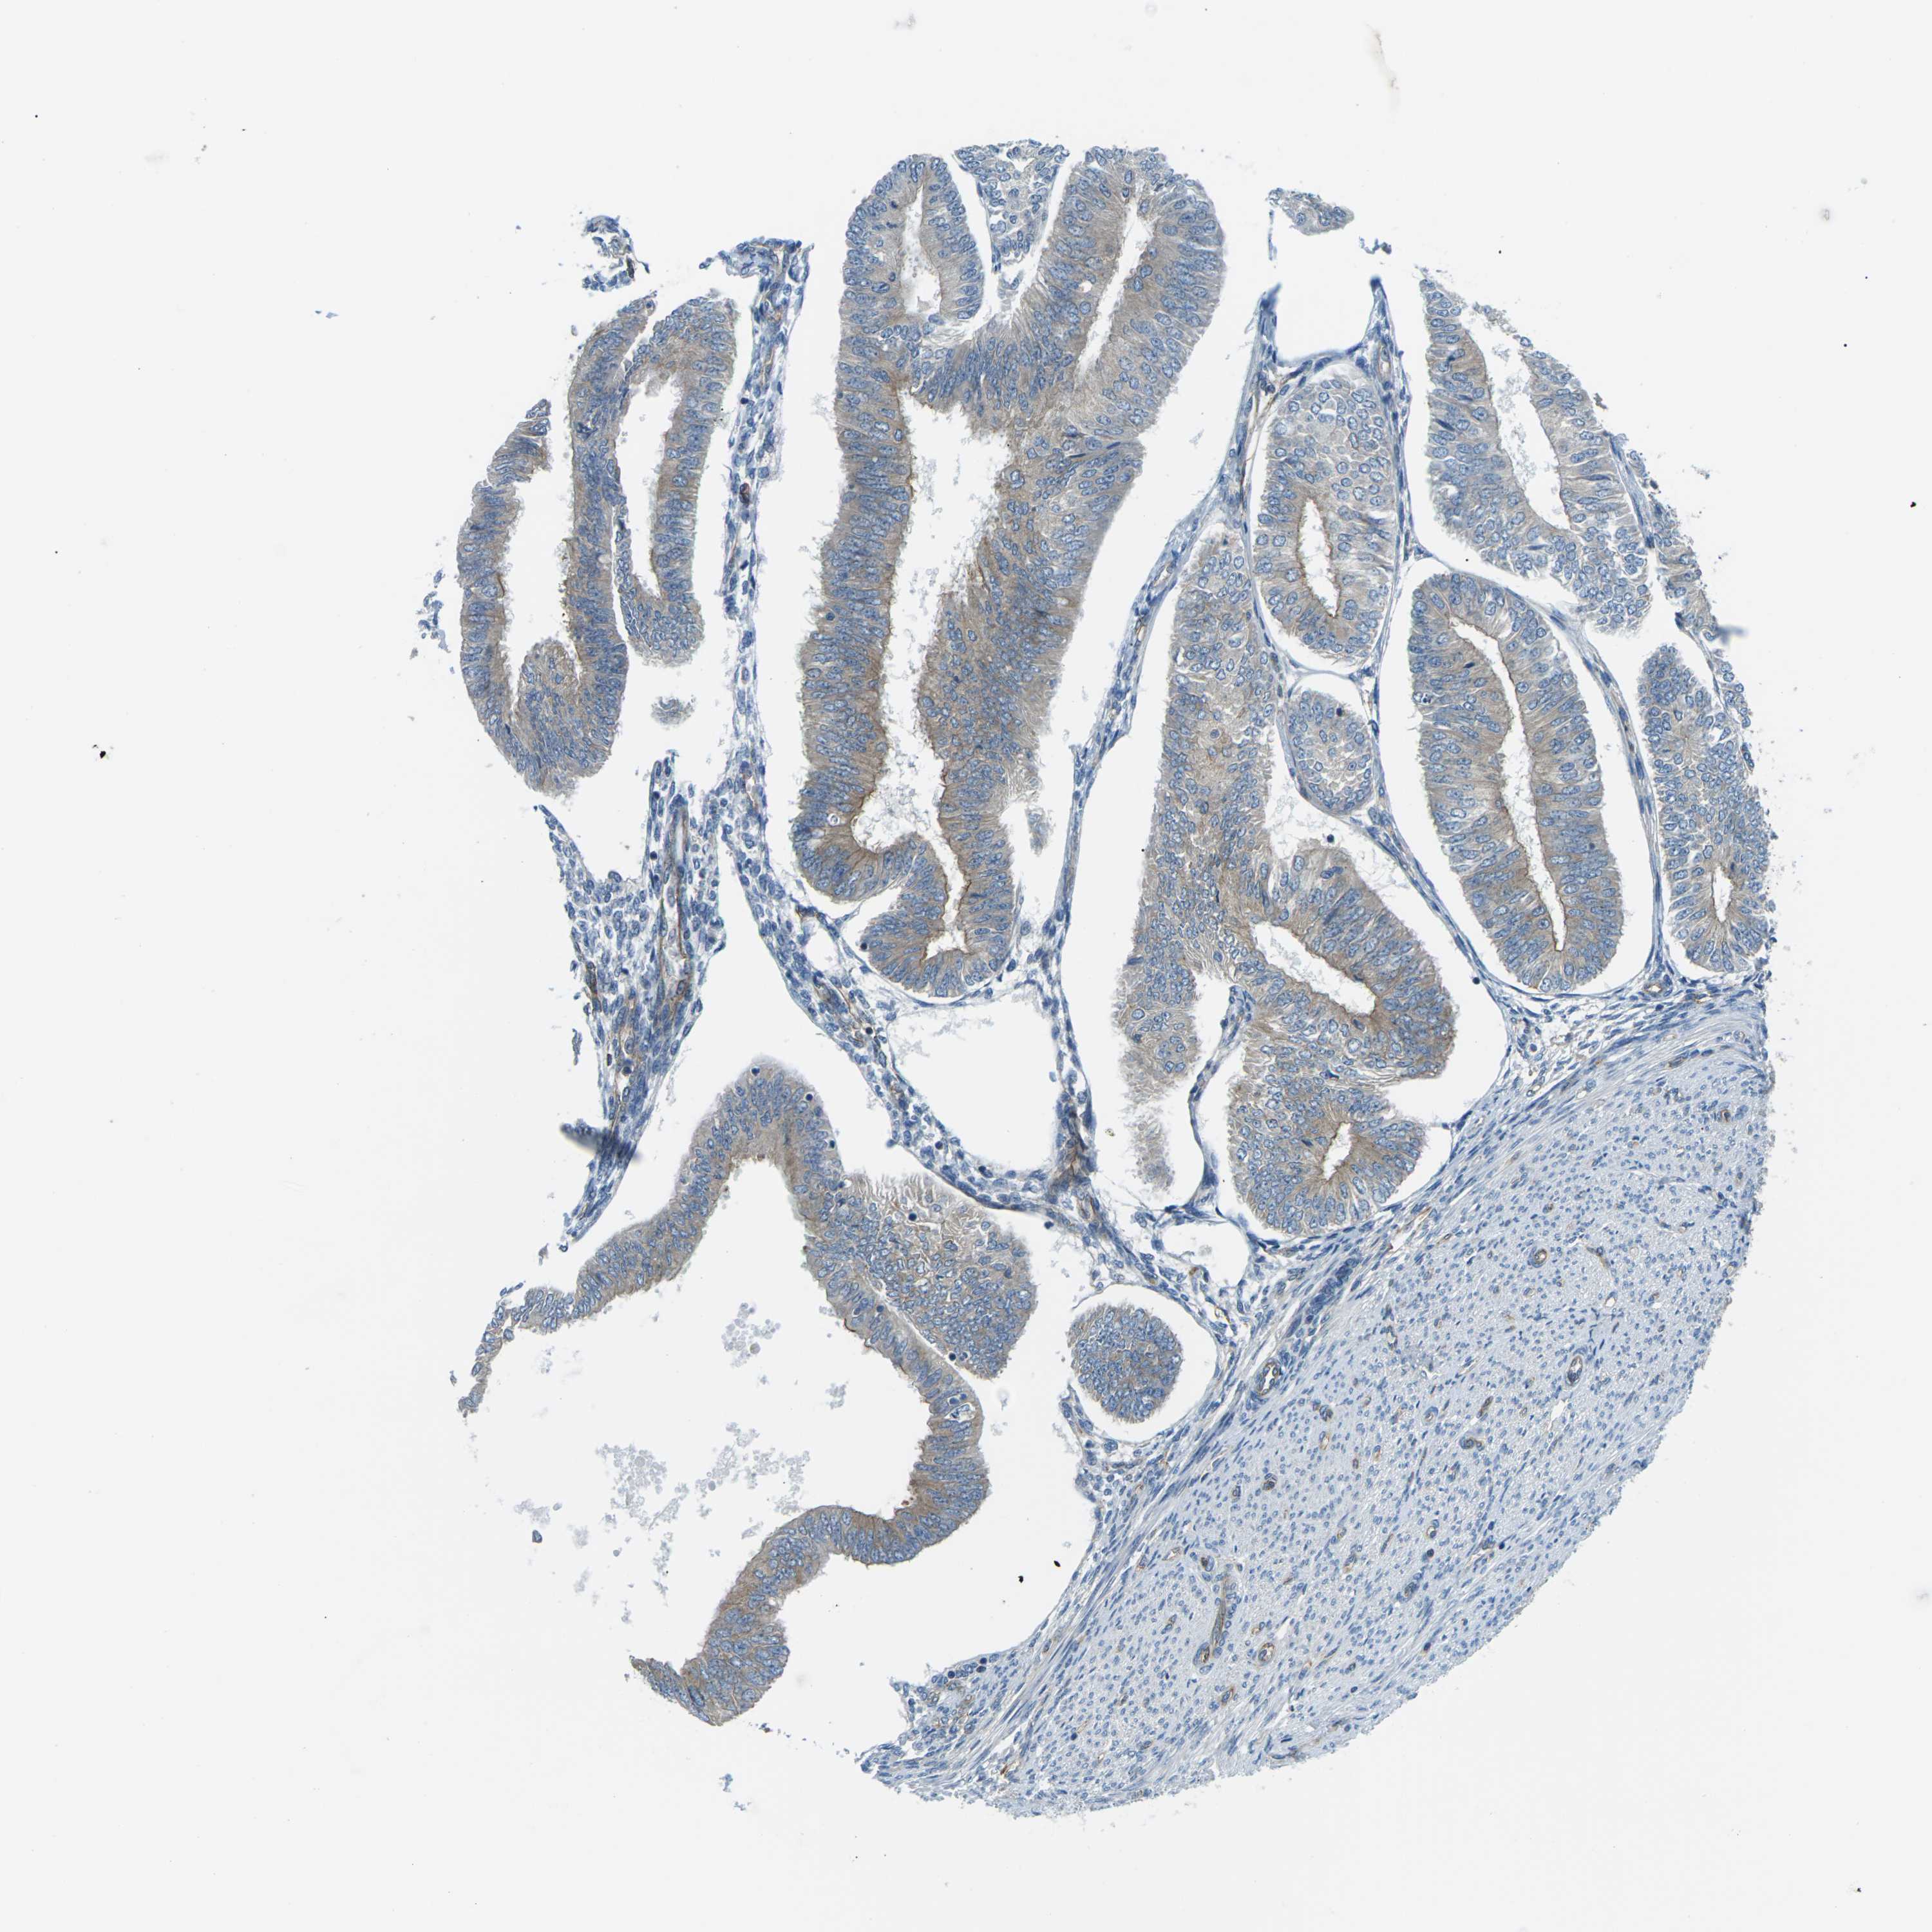

ENDOMETRIAL CANCER - Protein expressioni

A mouse-over function shows sample information and annotation data. Click on an image to view it in a full screen mode. Samples can be filtered based on level of antibody staining by selecting one or several of the following categories: high, medium, low and not detected. The assay and annotation is described here.

Note that samples used for immunohistochemistry by the Human Protein Atlas do not correspond to samples in the TCGA dataset.

Antibody stainingi

Antibody staining in the annotated cell types in the current human tissue is reported as not detected, low, medium, or high, based on conventional immunohistochemistry profiling in selected tissues. This score is based on the combination of the staining intensity and fraction of stained cells.

Each image is clickable and will lead to virtual microscopy that enables deeper exploration of all samples and also displays staining intensity scores, fraction scores and subcellular localization as well as patient and tissue information for each sample.

Antibody HPA014353

Antibody HPA014736

Staining

High

Medium

Low

Not detected

Intensity

Strong

Moderate

Weak

Negative

Quantity

>75%

75%-25%

<25%

None

Location

Nuclear

Cytoplasmic/membranous

Cytoplasmic/membranous,nuclear

Adenocarcinoma, NOS